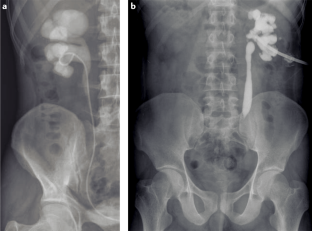

Gibson, M. S., Puckett, M. L. & Shelly, M. E. Renal tuberculosis. Radiographics 24, 1 (2004).

Roylance, J., Penry, B., Rhys Davies, E. & Roberts, M. Radiology in the management of urinary tract tuberculosis. Br. J. Urol. 42, 679–687 (1970).

Kollins, S. A., Hartman, G. W., Carr, D. T., Segura, J. W. & Hattery, R. R. Roentgenographic findings in urinary tract tuberculosis. A 10-year review. Am. J. Roentgenol. Radium Ther. Nucl. Med. 121, 487–499 (1974).

Sallami, S. et al. Imaging findings of urinary tuberculosis on computerized tomography versus excretory urography: through 46 confirmed cases. Tunis. Med. 12, 743–747 (2014).

Gaudiano, C. et al. Multidetector CT urography in urogenital tuberculosis: use of reformatted images for the assessment of the radiological findings. A pictorial essay. Abdom. Radiol. 9, 2314–2324 (2017).

Wang, L. J. et al. Imaging findings of urinary tuberculosis on excretory urography and computerized tomography. J. Urol. 169, 524–528 (2003).